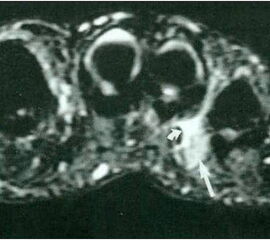

• MRT (in Bauchlage!) 7